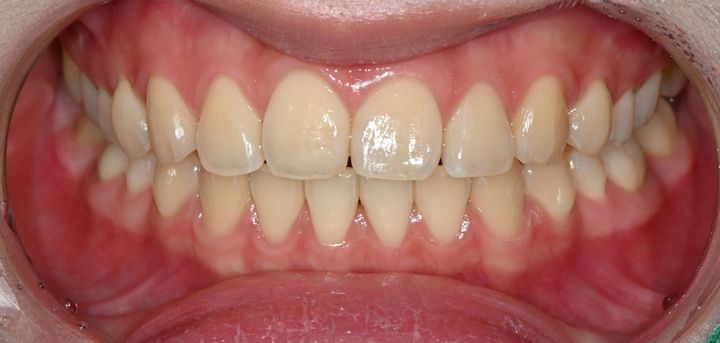

ハル歯科医院は、最先端のインプラント歯科治療に特化したクリニックです。代表のジョー・ハング院長は日本の神奈川歯科大学を卒業し、両国での歯科医師免許を保持。さらに、韓国で専門医資格を取得し、口腔外科など高度な手術経験も豊富です。すべての治療を院長自らが行う専任診療制を採用しており、流暢な日本語で対応可能。「デジタルインプラント」や「無削除ラミネート」などの最新のデジタル歯科治療を、日本の約半額で受けられます。仁川・金浦空港から乗り換えなしで行ける孔徳(コンドッ)駅すぐとアクセスも良好で、旅行者にも便利な立地となっています。

もうすぐ在韓5年になる者です。今まではクリーニングも治療も他院でやってもらっていましたが、自分の住んでいるアパートの目の前にハル歯科さんがあることを最近知り早速コンタクトをとりました。先生は流暢な日本語、というより日本人にしか感じられない、柔らかく丁寧な日本語をお話しになりスタッフさん達も皆さん対応が素晴らしいです。まずはそこに安心しました。これから銀歯を白い歯にしてもらう予定ですが、信頼のおける歯医者さんに出会えてよかったです♡

ソウル在住もうすぐ5年になる者です。今まで何かトラブルがあったりクリーニングをする時には、他の先生のところに通っていたのですが…自分の住んでいるアパートの目の前にあるハル歯科さんを見つけて、コンタクトをとりました。先生はもちろん受付の方や他のスタッフの方も、みなさん柔らかく優しい物腰で…小さいお子様から年配の方まで安心して(お任せ)できる歯医者さんだと思います。コンドクの駅の直近で、医院の中も清潔で十分広いです。ちなみに私は子供のころに虫歯になり銀歯になってしまったものをきれいな白い歯にしてもらいます。型を取ったところで、三日後に装着で^^楽しみです♡